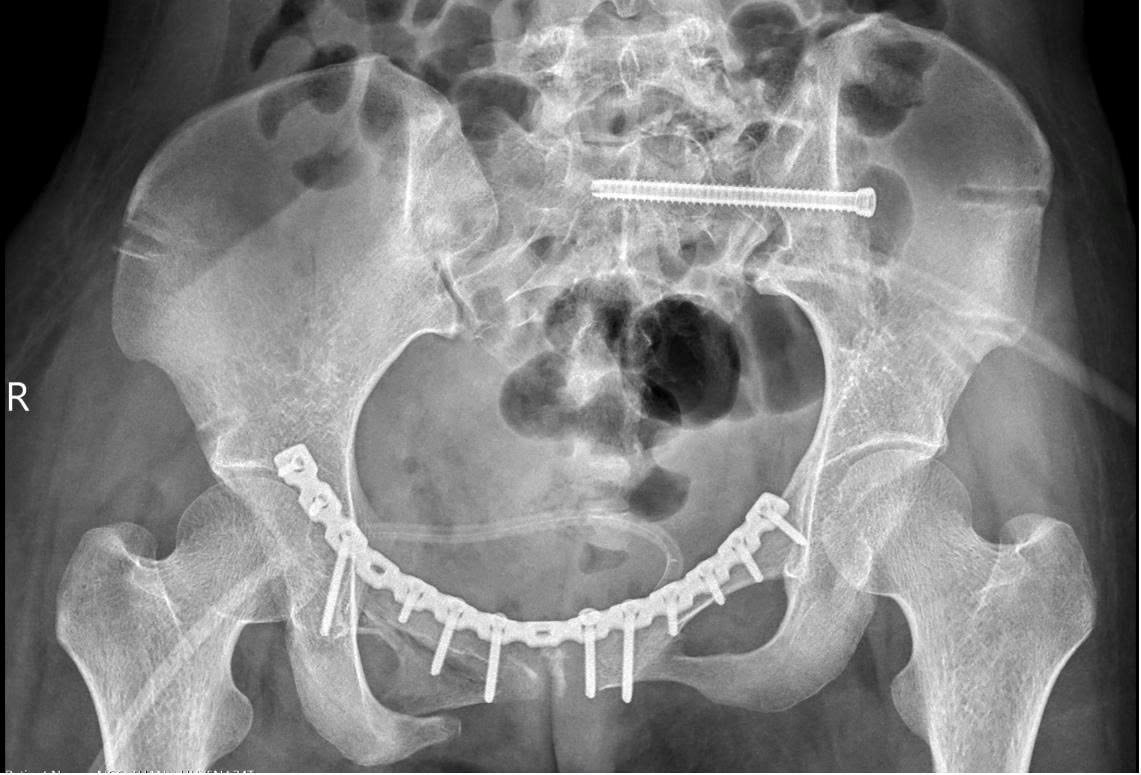

Sau nhiều giờ khẩn trương trong phòng mổ, ê-kíp phẫu thuật đã ngăn chặn được tình trạng sốc đa chấn thương, cầm máu thành công và giành lại sự sống cho bệnh nhân. Sau 2 tuần điều trị tích cực, khi huyết động ổn định, bệnh nhân được tháo cố định ngoài và phẫu thuật lần hai để nắn chỉnh lại các di lệch (có sử dụng công nghệ in 3D giúp tiên lượng mức độ khó của phẫu thuật và chọn các nắn chỉnh khung chậu và vị trí đặt nẹp) kết hợp xương bằng nẹp vít bên trong, giúp cố định vững chắc khung chậu. Đến ngày 6/10, bệnh nhân có thể ngồi dậy và xuất viện về nhà.

“Vì vậy, mục tiêu điều trị là phục hồi cấu trúc giải phẫu khung chậu và cố định vững chắc bằng nẹp vít, giúp bệnh nhân sớm vận động trở lại. Ở trường hợp này, khung chậu mất vững cả cung trước và sau, nên sau khi nắn chỉnh, chúng tôi cố định cung trước bằng nẹp vít và cung sau bằng vít xốp”. – Bác sĩ Khanh chia sẻ.